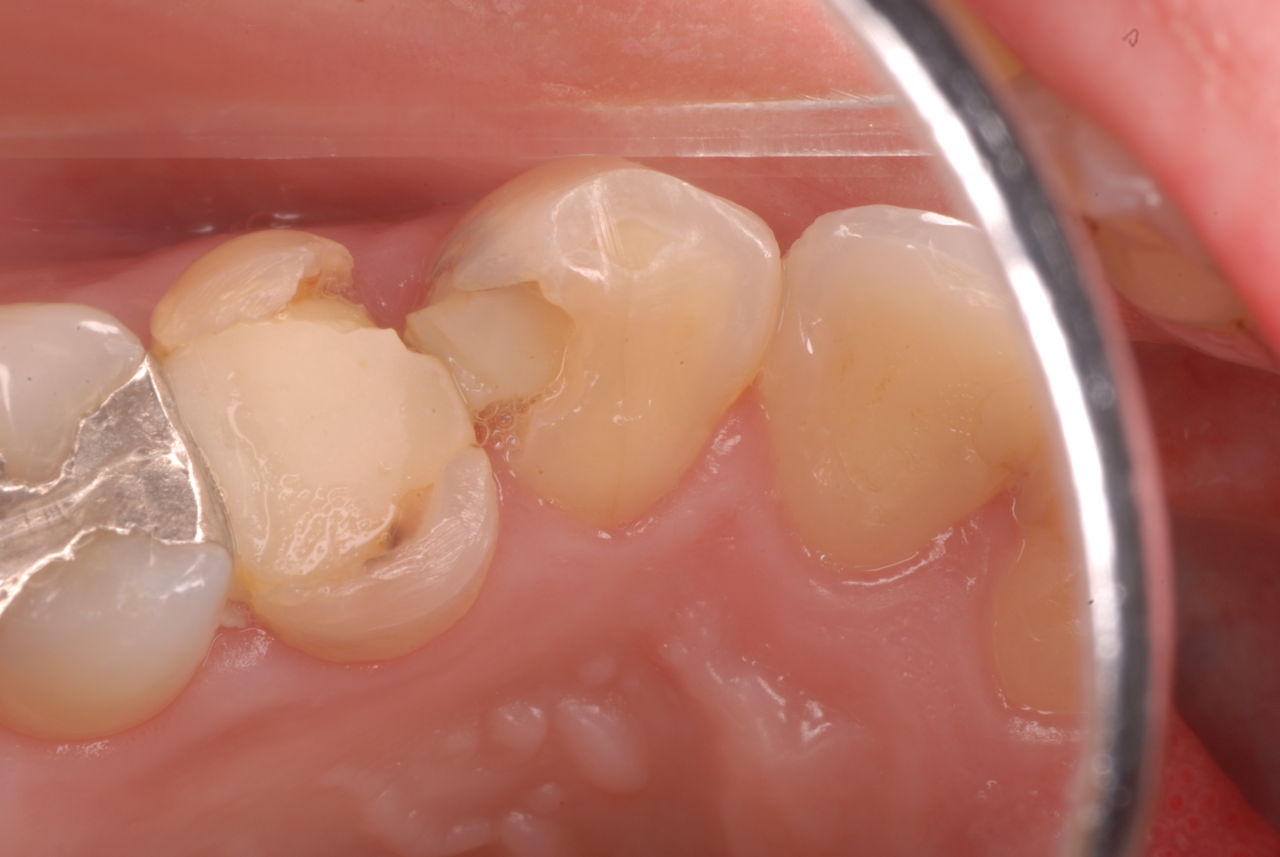

入れ歯の話から入りました。色々不満で注文があるようです。でも話が一段落して口腔内を調べると殆どの歯が重症で抜けそうな歯だらけなのです。

ご自分でやられても歯茎から血が出ないと話をされていましたが、私がブラシを当てると悲惨な状態であることがわかりました。

何故歯が悪くなるのか、歯周病で抜けるのか分からなければ何を入れても歯は悪くなり抜けていくのです。

病気を治しましょう。それから差し歯や入れ歯を入れましょう!物を入れれば入れるほど、磨き方や掃除の仕方が上手にならなければ、すぐ抜けてくるのです。